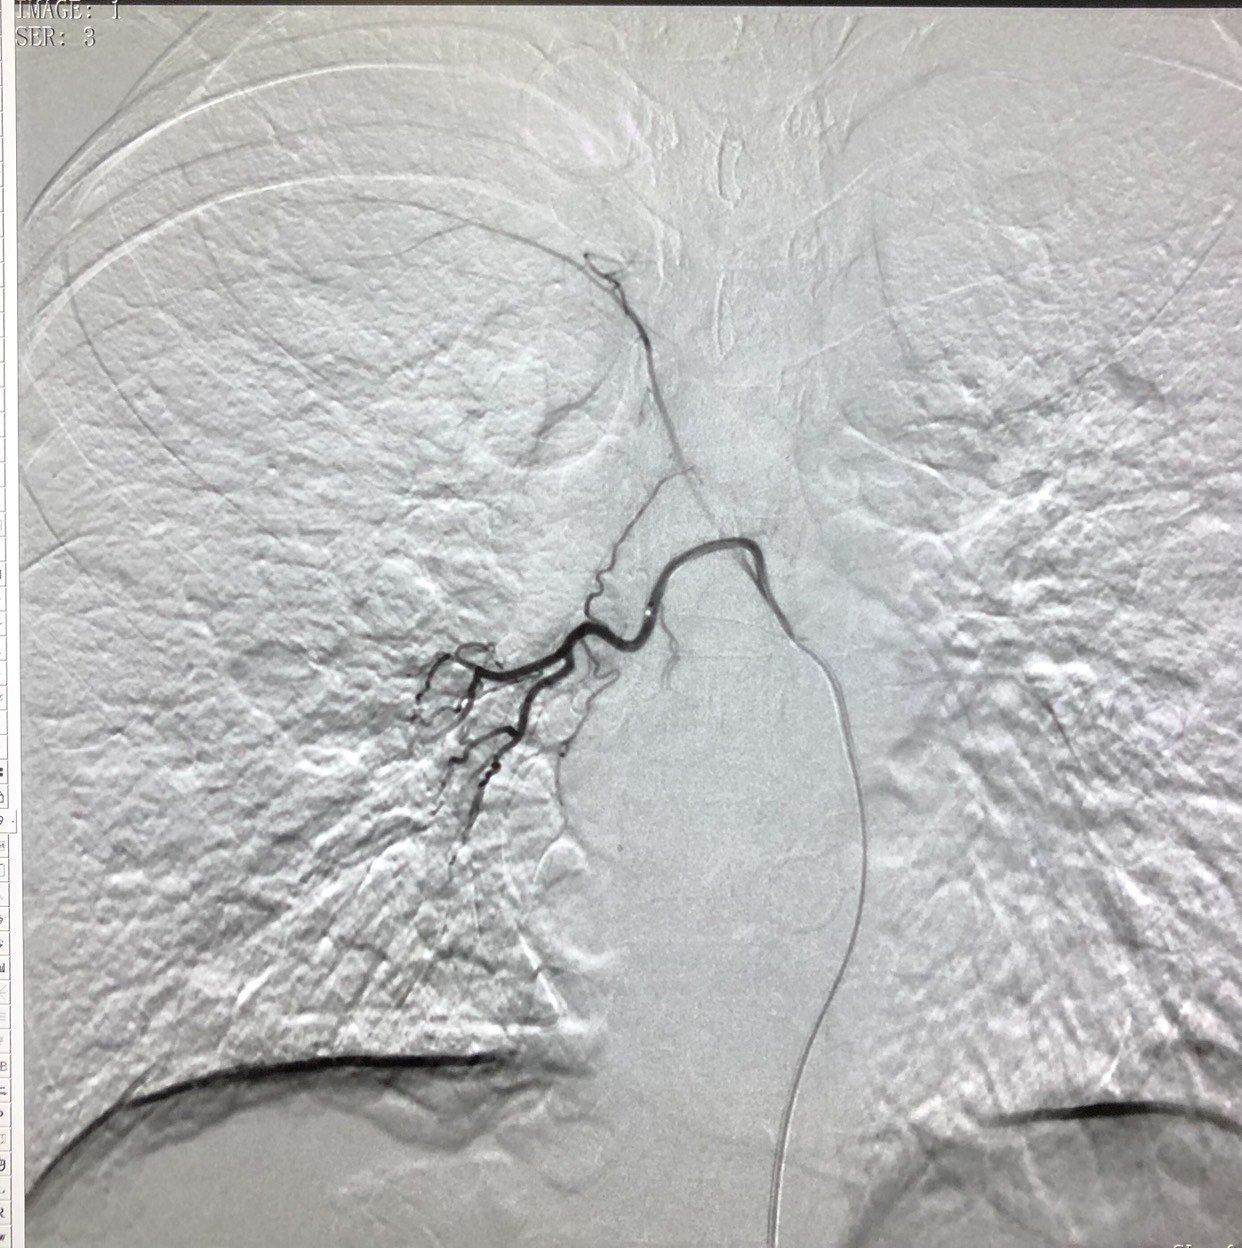

右侧支气管动脉造影见右侧肺门肿瘤染色明显。